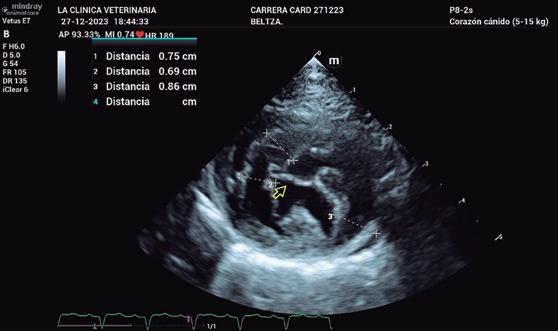

• Modo B: en la proyección paraesternal derecha eje largo, se observó un jet de regurgitación mitral con dirección posterior y SAM (figura 3). En el eje corto derecho a la altura de la base cardiaca se observó un ratio atrio izquierdo/aorta (AI/Ao) de 1,92 (>1,6 se considera dilatación AI) (figura 4). Además, se observó hipertrofia de la pared del septo interventricular (SIV) de 7,6 mm y la pared libre del ventrículo izquierdo (PLVI) la 8,4 mm (hipertrofia >6 mm) (figura 5).

• Forma endomiocárdica: se distingue por disposición de bandas fibrosas de tejido en el ventrículo izquierdo que forman puentes entre la pared libre y el septo interventricular o los músculos papilares (figura 2), o bien infiltración difusa de este tejido envolviendo el ventrículo izquierdo; a veces se denomina “cicatriz endomiocárdica”.

Aunque los hallazgos no están uniformemente aceptados2,3,5, se observa dilatación del atrio izquierdo (con posible regurgitación mitral leve), o de ambos atrios; a nivel

de ventrículo izquierdo (también del derecho en algunas ocasiones2), dependiendo de la forma de presentación, observaremos miocardio o endomiocardio hiperecoico de forma uniforme o con asimetría y áreas de adelgazamiento. O bien, presencia de bandas fibrosas, áreas de distorsión o unión de los músculos papilares.2,3,5 Otras pruebas diagnósticas interesantes para el diagnóstico son:

En la ecocardiografía se advierte un aumento del tamaño de cámaras cardiacas derechas (figura 4) y regurgitación tricúspide evidenciada con Doppler color. El movimiento de la pared libre del ventrículo derecho puede estar reducido en algunos gatos, mientras que el del septo interventricular puede ser paradójico. La cavidad del ventrículo izquierdo puede ser normal o estar disminuida, aunque la aurícula izquierda puede estar aumentada en algunos gatos.3